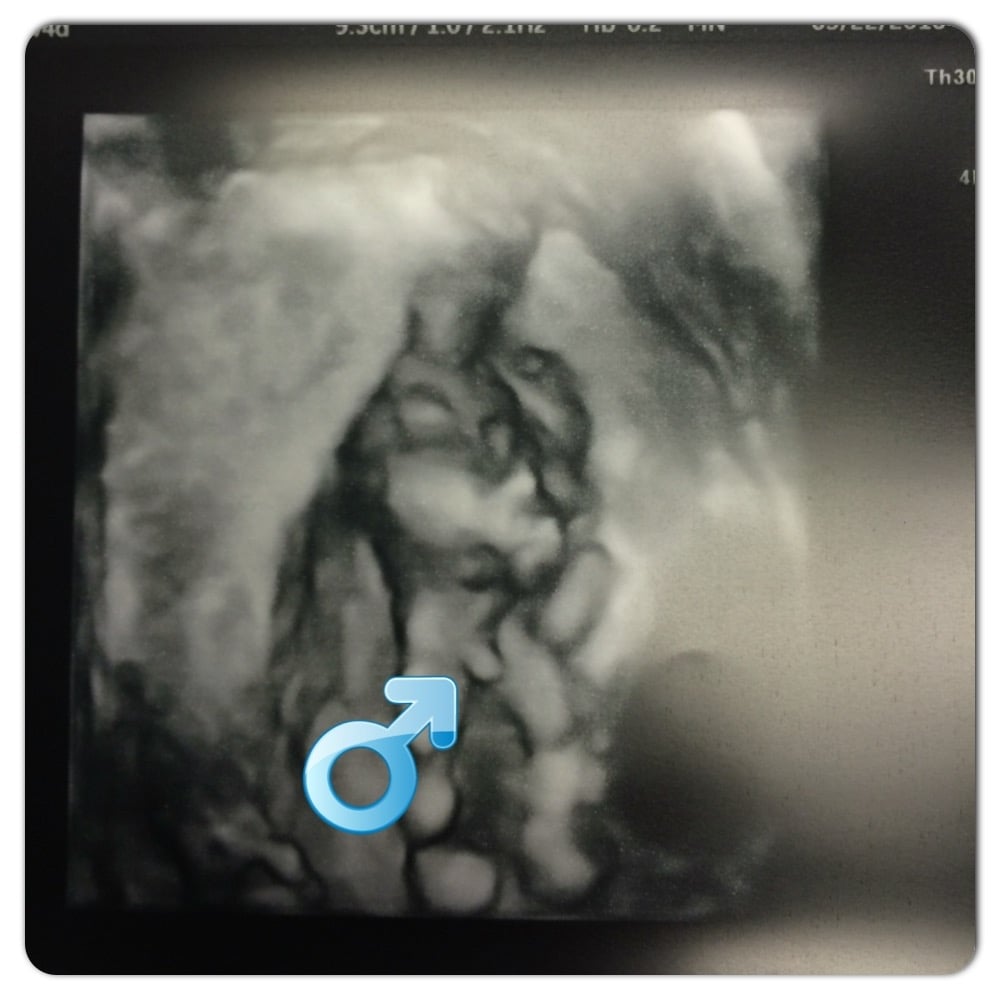

@Akiratani- Woops! Guess there's that 10-20% margin of error he gave you. Did you have another scan or genetic testing done? Either way, congrats on the boy!

I had another scan at a specialty ultrasound place. She spent about 15 min getting it from 6 different angles. She said there was no way around it, definitely a boy haha. I was hoping this would be my girl since I already have 2 boys and this is our last, but oh well I am just glad that I know now and that he is healthy.